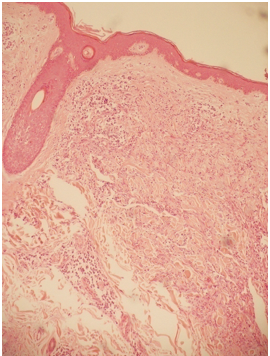

•Billy’s skin biopsy shows Kaposi’s sarcoma.This is an HIV AIDS defining disease.There is a big lesion composed of proliferating blood vessels.These are the histological features of Kaposi sarcoma.This is an AIDS defining diagnosis